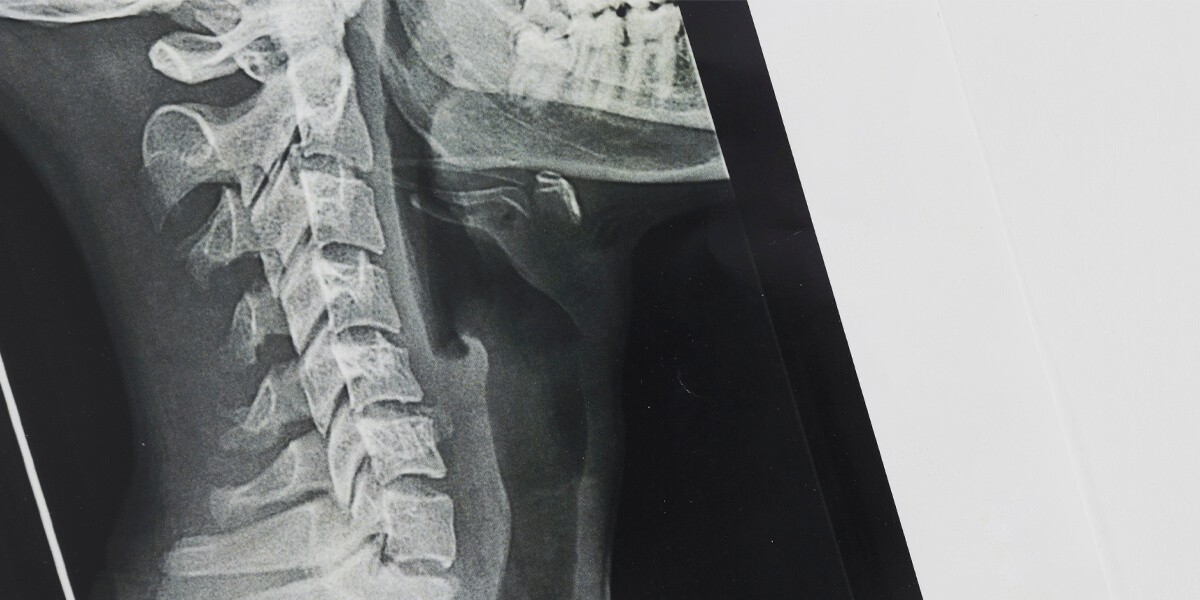

Os exames digitais permitem maior agilidade na aquisição dos mesmos e possibilitam ao médico assistente radiografias de altíssima qualidade. Além da precisão e do conforto gerado, os equipamentos digitais descartam o uso de agentes químicos para a revelação dos exames, colaborando com o meio ambiente.

Os exames radiológicos podem ser enviados por meio digital ao paciente e ao médico assistente.